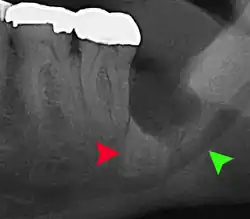

| 3D CT of an impacted wisdom tooth adjacent the inferior alveolar nerve prior to removal of wisdom tooth | |